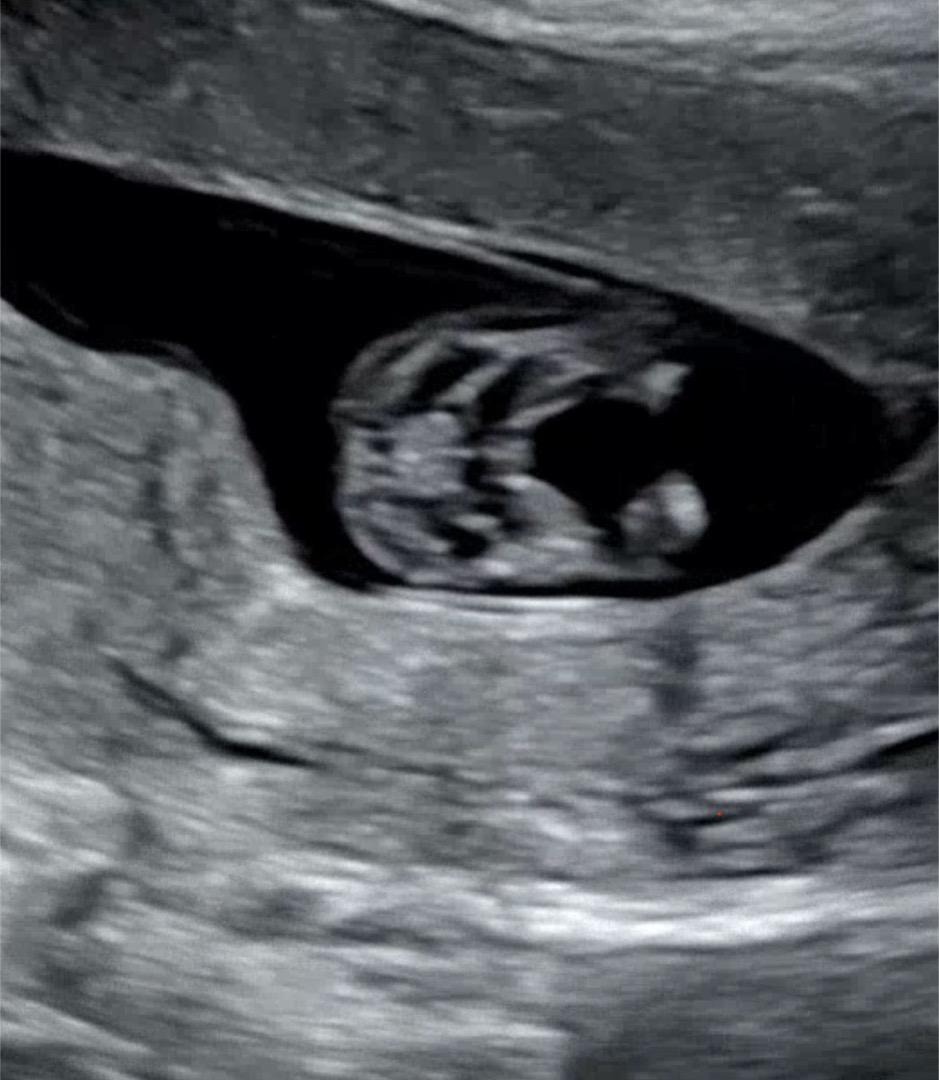

12주차!! 아들!?딸!?!?

12주차 정밀초음파 봤는데 아들일까요!?? 🤔